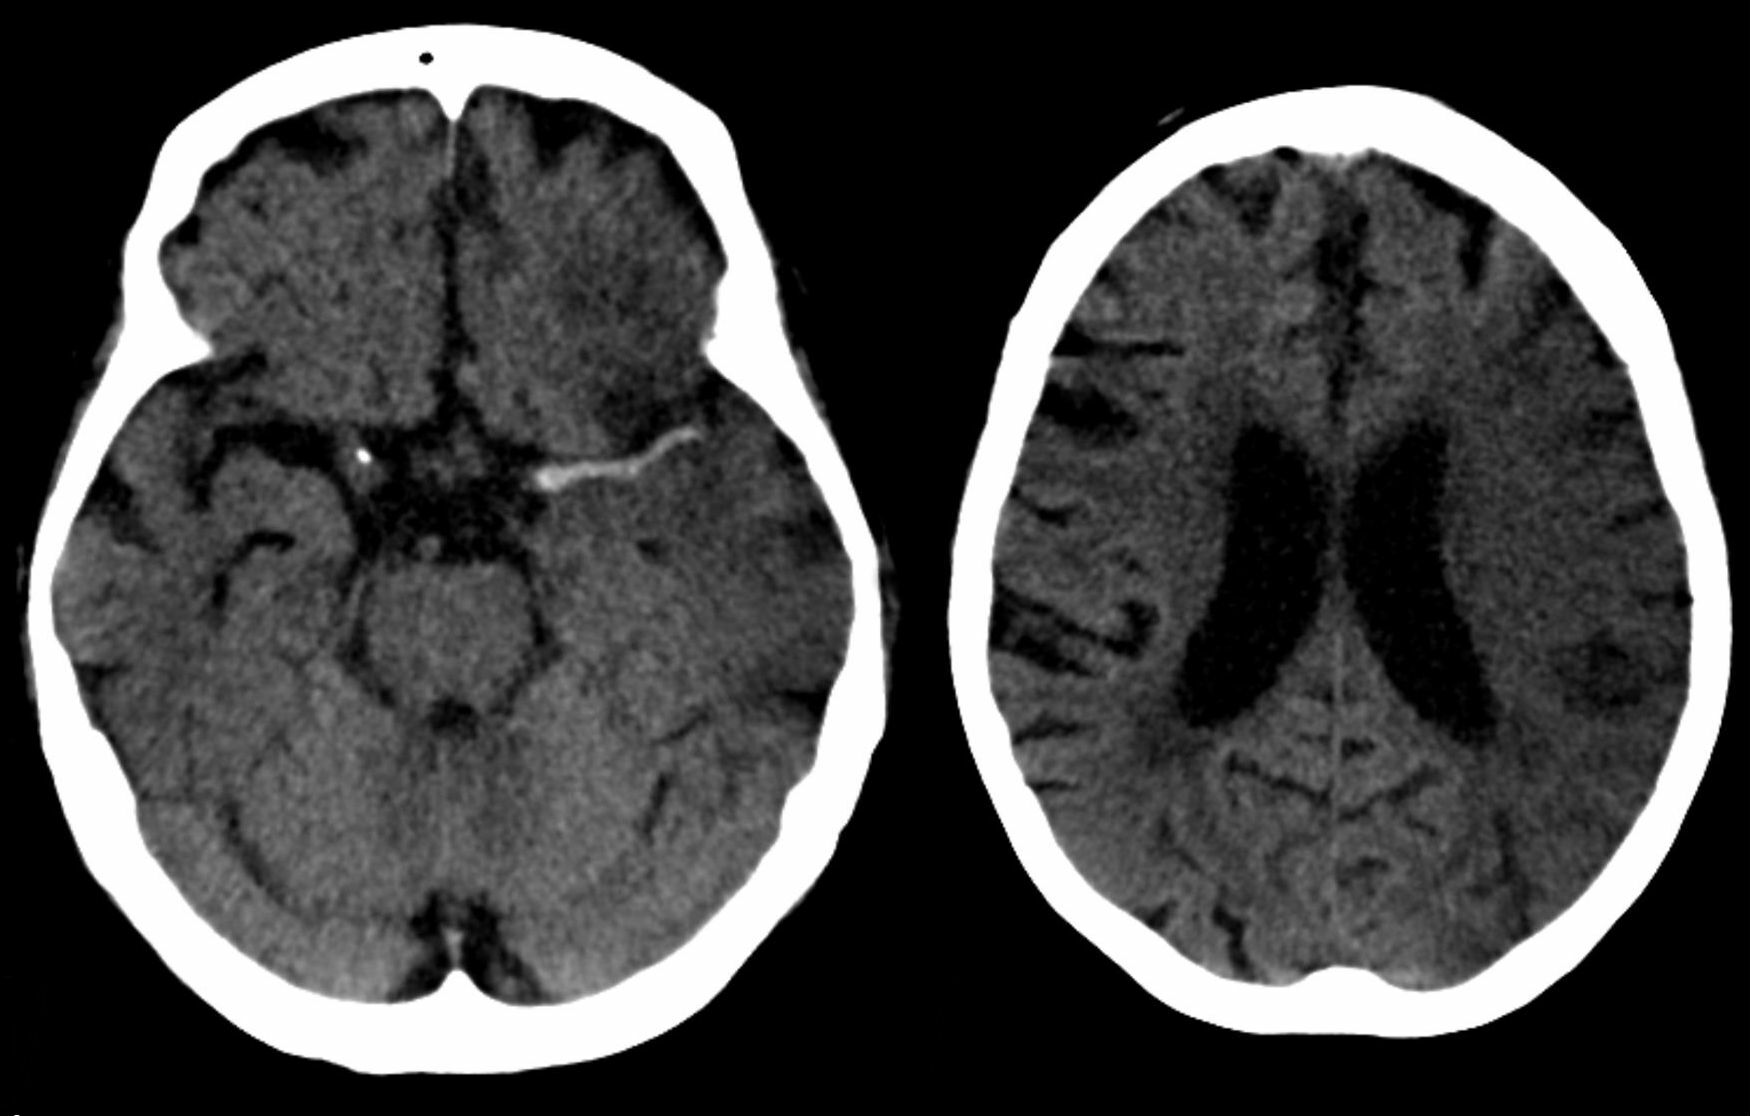

뇌졸중은 신경학적 검사(예: NIHSS) , CT 스캔(대부분 조영제 증강 없이), MRI 스캔, 도플러 초음파, 혈관조영술 등 여러 가지 방법으로 진단한다. 뇌졸중 자체의 진단은 영상 기술의 도움을 받아 임상적으로 이루어지며, 영상 기술은 뇌졸중의 아형과 원인을 결정하는 데에도 도움이 된다.[74] 뇌졸중 진단을 위한 혈액 검사는 아직 일반적이지 않지만, 혈액 검사는 뇌졸중의 원인을 파악하는 데 도움이 될 수 있다.[74] 사망한 사람의 경우 뇌졸중 부검을 통해 뇌졸중 발생 시점과 사망 시점 사이의 시간을 확인할 수 있다.

뇌졸중은 신경학적 검사(예: NIHSS) , 컴퓨터 단층촬영(CT) (대부분 조영제 증강 없이), 자기공명영상(MRI) 스캔, 도플러 초음파, 및 혈관조영술 등 여러 가지 방법으로 진단됩니다. 뇌졸중 자체의 진단은 영상 기술의 도움을 받아 임상적으로 이루어집니다. 영상 기술은 뇌졸중의 아형과 원인을 결정하는 데에도 도움이 됩니다.[74]

응급 상황에서 허혈성 뇌졸중(혈관이 막혀서 발생)과 출혈성 뇌졸중(혈관이 터져서 발생)을 진단하기 위해 CT와 MRI가 사용됩니다.

MRI는 만성 출혈을 감지하는 데 더 민감합니다.[76] CT는 특히 뇌졸중이 작거나, 최근에 발생했거나,[12] 뇌간이나 소뇌 부위(후순환 뇌경색)에 있는 경우 허혈성 뇌졸중을 감지하지 못할 수 있습니다. MRI는 확산 강조 영상을 사용하여 후순환 뇌경색을 감지하는 데 더 효과적입니다.[77] CT는 특정 뇌졸중 모방 질환을 배제하고 출혈을 감지하는 데 더 많이 사용됩니다.[12]